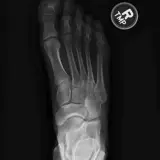

Over 2,100 interactive radiology cases, curated by radiologists for your level of training. Scroll, window, and view cases full screen — just like on PACS. Click linked findings in each writeup to jump straight to them on the image. Cases include sample reports, a focused discussion section, original illustrations, and videos.

完全交互式病例,配备您在 PACS 上期待的各项工具——滚动、调窗、缩放、平移、测量、ROI 和全屏模式。

丰富的标注直接在病例图像上突出关键发现。点击病例讲解中的关联发现,即可跳转至其在扫描上的精确位置。